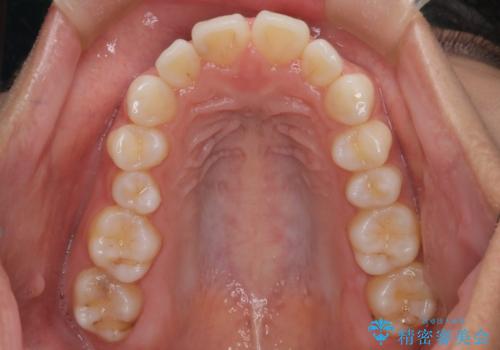

【インビザライン】前歯の後戻りを再矯正

- 前歯が出ていることを主訴に来院されました。検査の結果、口元が標準より出ているわけではなかったため今回はIPRと拡大をし、非抜歯で治療を行いました。

非抜歯でも歯軸の向きを改善したことで前歯が下がり、出っ歯に見えてしまうという主訴が改善しました。